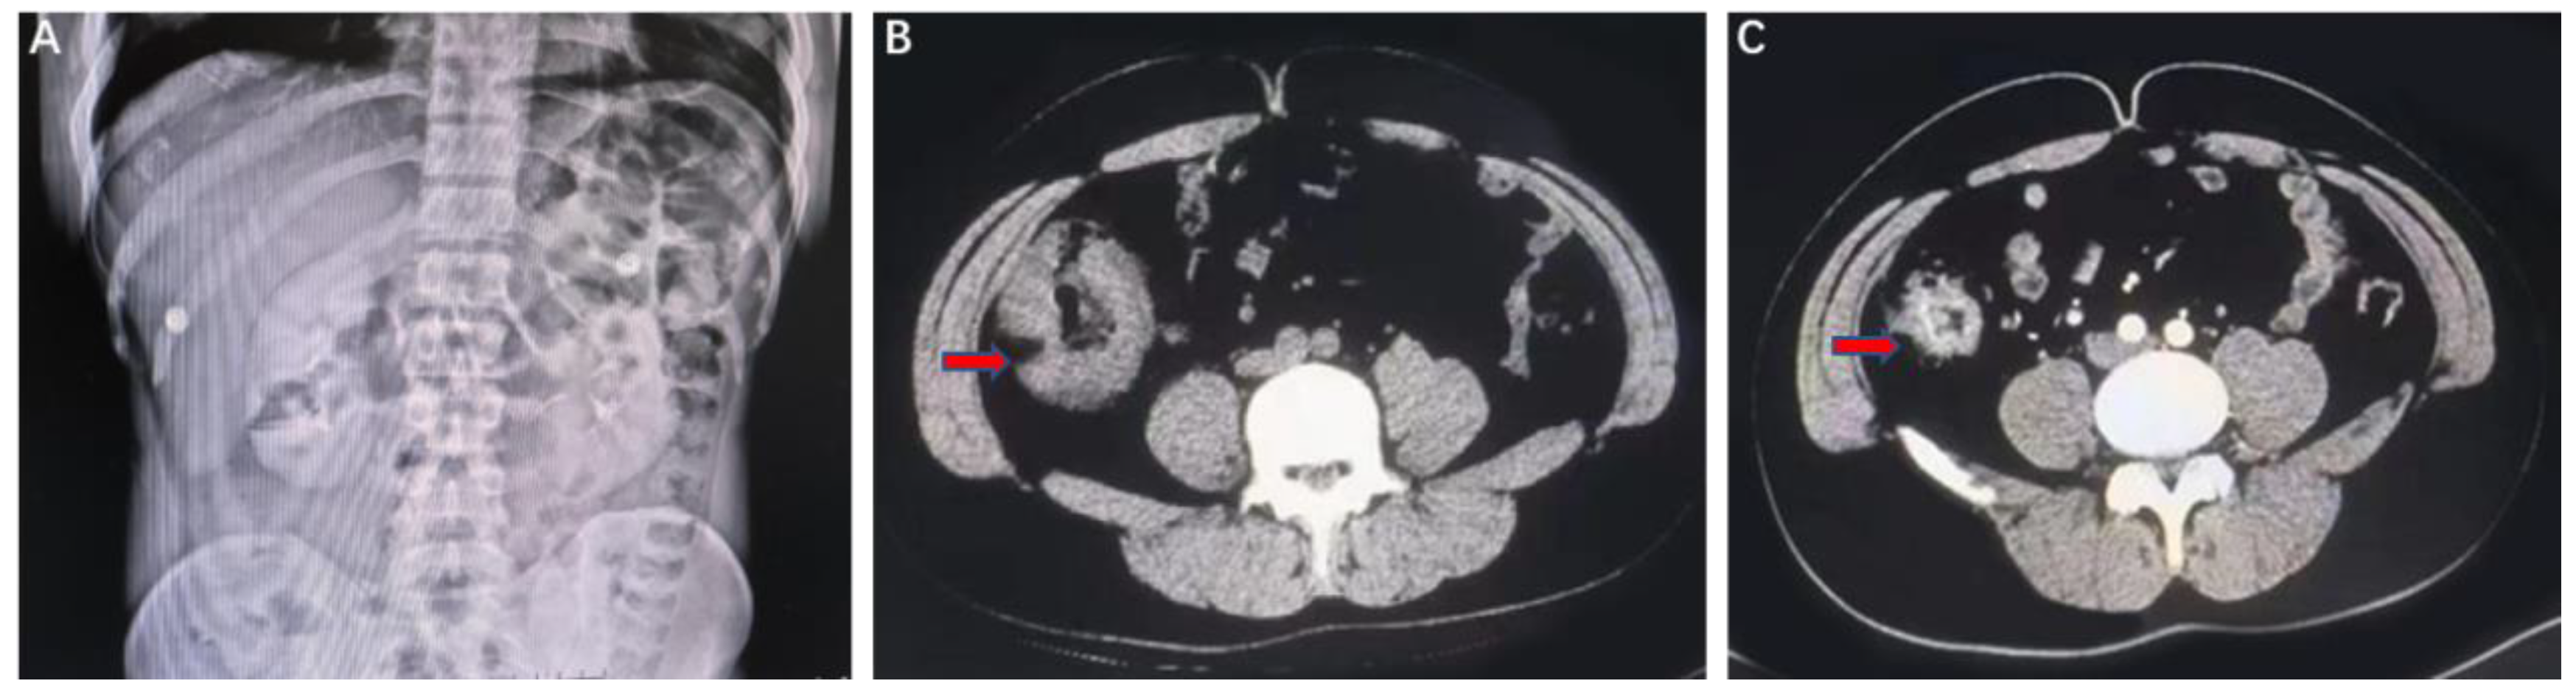

2. Case Presentation